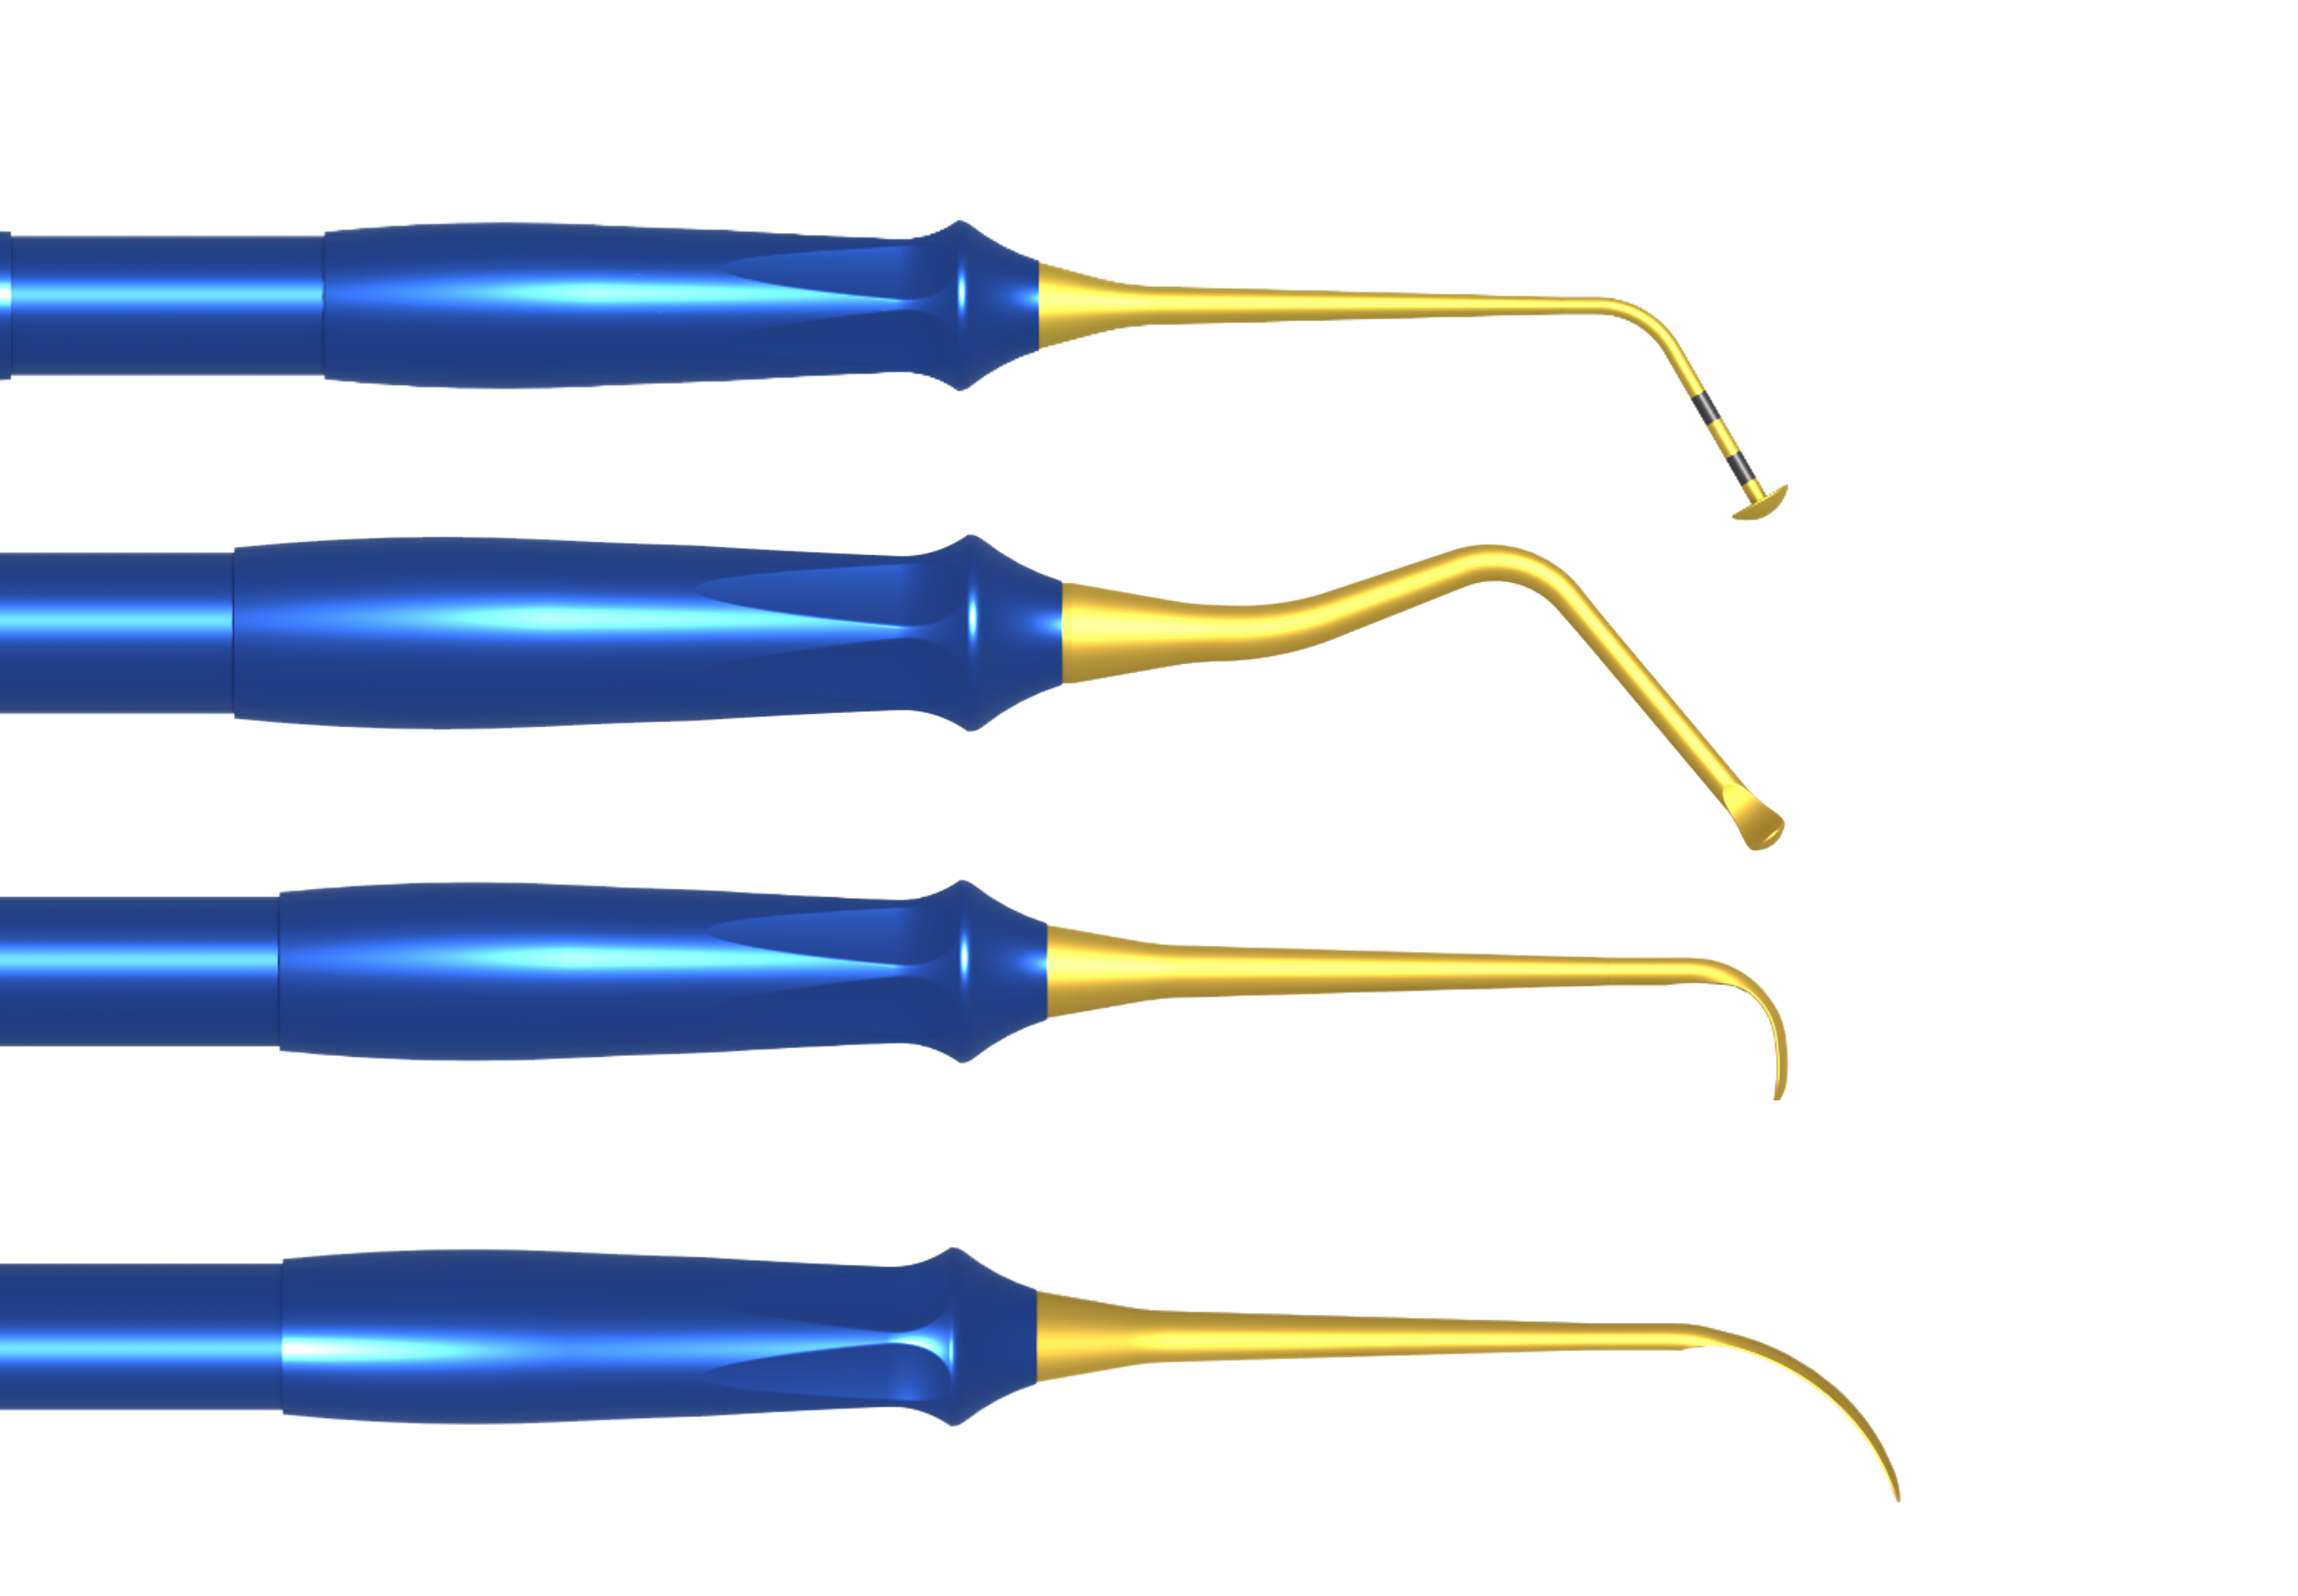

Hand Instrument

Designed for fine force control during delicate procedures. Supports precise membrane detachment and elevation.